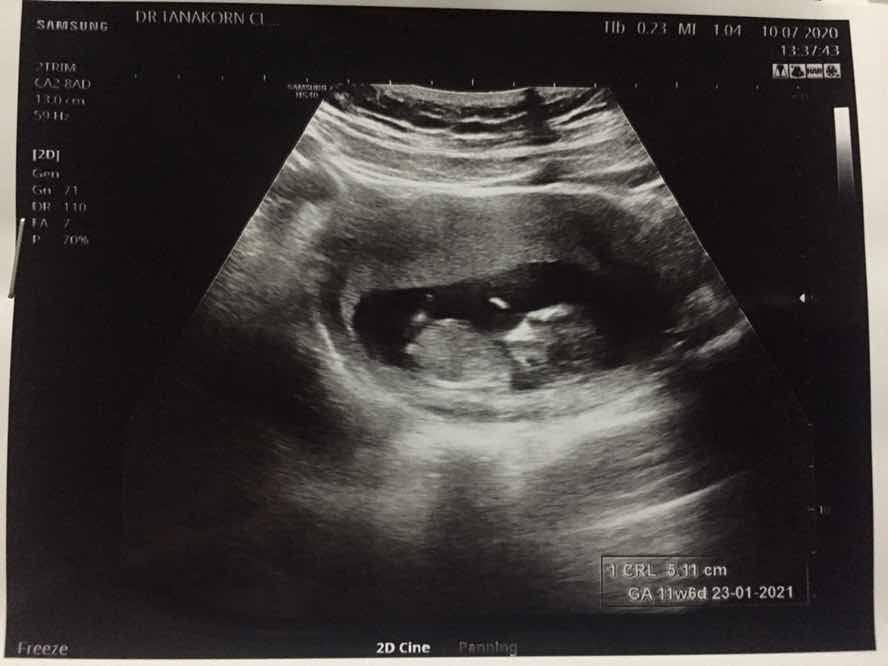

11 สัปดาห์ ซาวด์มาเจอลูกแบบนี้ถือว่าเขาตัวใหญ่ไหมคะหรือปกติ

11สัปดาห์เหมือนกันคะ

11วิค ตอนนี้จะ13แล้ว